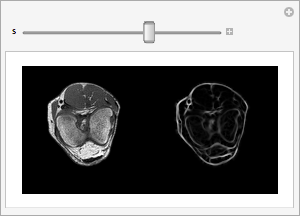

脊线过滤器突出显示在强度分布中具有高的主曲率的体元. 下面的例子是把它应用于肌肉组织间的筋膜.

并行渲染线原始的和滤波后的膝盖的每个切片.